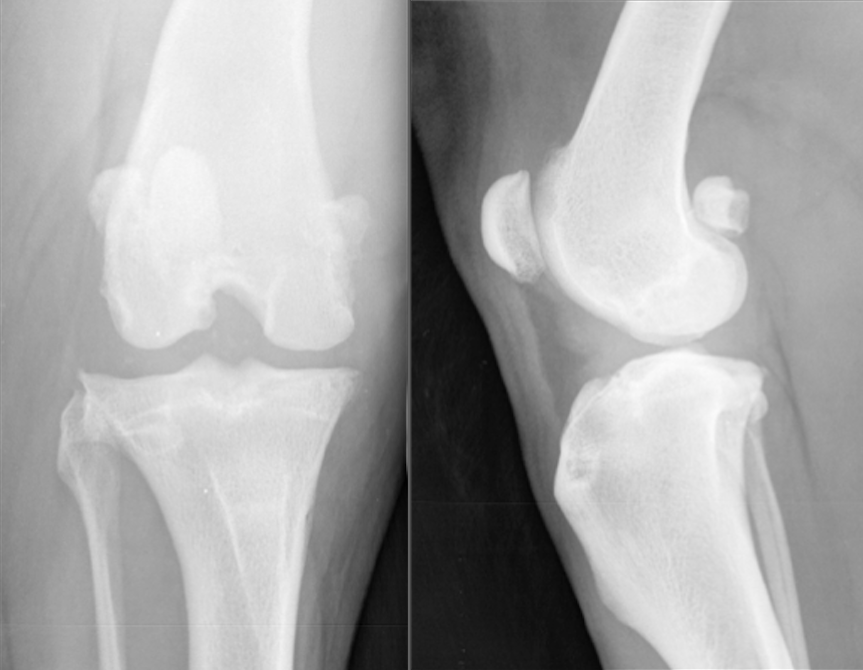

Røntgen! - Lav 2 ortogonale billeder - Evt oblique og stress også

Hvordan ser korsbånd ud på røntgenbilleder?

De er soft tissue = ikke på røntgen

Hvordan hæftes patella fast?

4 steder:

Hvor ses hhv degenerative ændringer og hævelser oftest?

Grønne cirkler: degenerative ændringer

Røde streger: hævelser